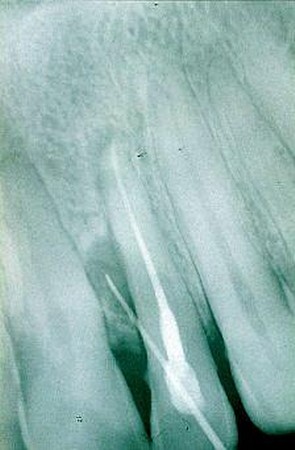

Orthopanthomografické (OPG) a intarorálne RTG snímkovanie je nevyhnutné pre stanovenie presnej diagnózy a plánu ošetrenia, pri preventívnych prehliadkach, ale aj pri bežnom ošetrení. Zobrazí už počiatočné kazy na miestach, ktoré nie sú na prvý pohľad viditeľné. Rovnako je dôležité aj pri endodoncii, teda pri ošetrení koreňových kanálikov, pri zápaloch nervu, pri paradentóze a kývavosti zubov, prípadne posúdení nutnosti extrakcie zuba.

V našej praxi sa pri diagnostike ochorení v dentoalveolárnej oblasti používa zobrazovacia technika, ktorá je neoddeliteľnou súčasťou vyšetrenia pacienta, ako aj následných ošetrení. Zhotovujeme digitálne intraorálne snímky. Ich výhodou je okamžité zobrazenie na monitore počítača, niekoľkonásobne znížená doba expozície, možnosť uloženia záznamu pre porovnanie do budúcnosti, možnosť aktívnej práce so snímkami, zobrazenie detailov, zmena kontrastu, farebné zobrazenie. Tieto snímky majú výrazný informatívny význam pri diagnostike tvrdých tkanív (zuby, kosti), závesný aparát zubov, pre plánovanie protetických prác, celkových sanácií, ale predovšetkým pri plánovaní implantačnej terapie.